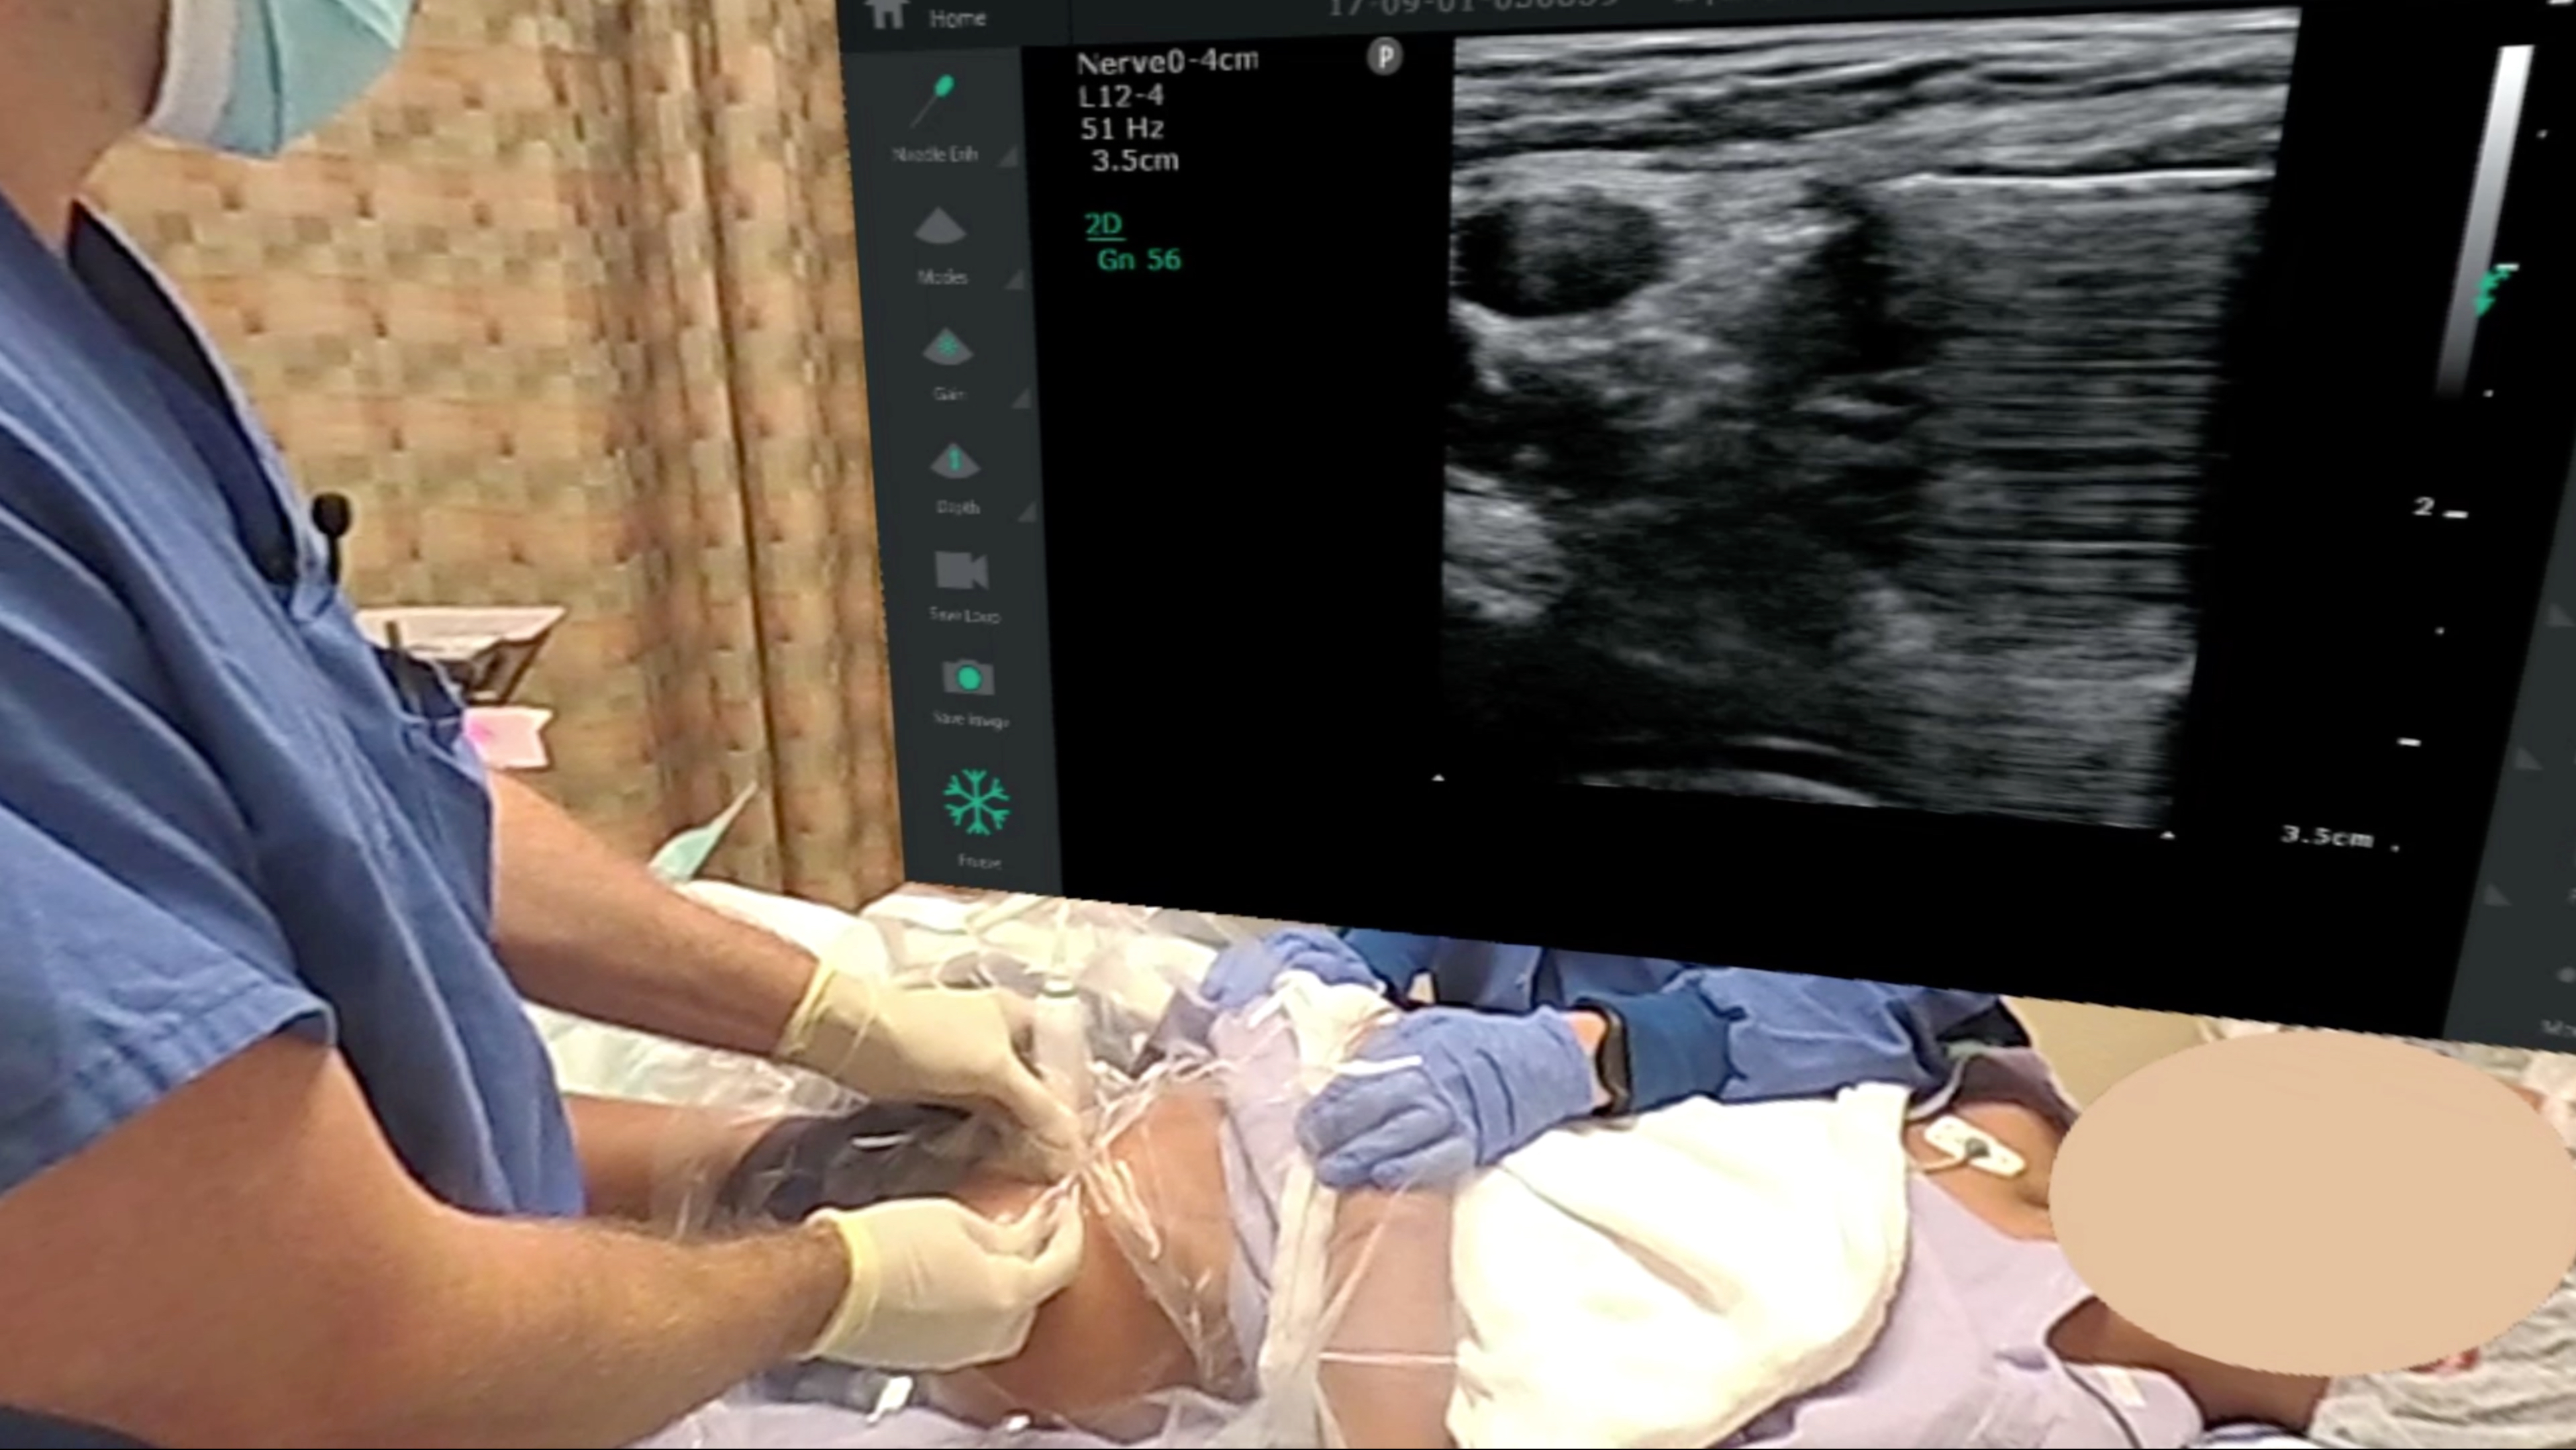

Dr. Scott Thomas performs a continuous ultrasound guided femoral catheter for ACL reconstruction using the Contiplex C catheter kit from B-Braun, while Dr. Brandon Winchester annotates the procedure.